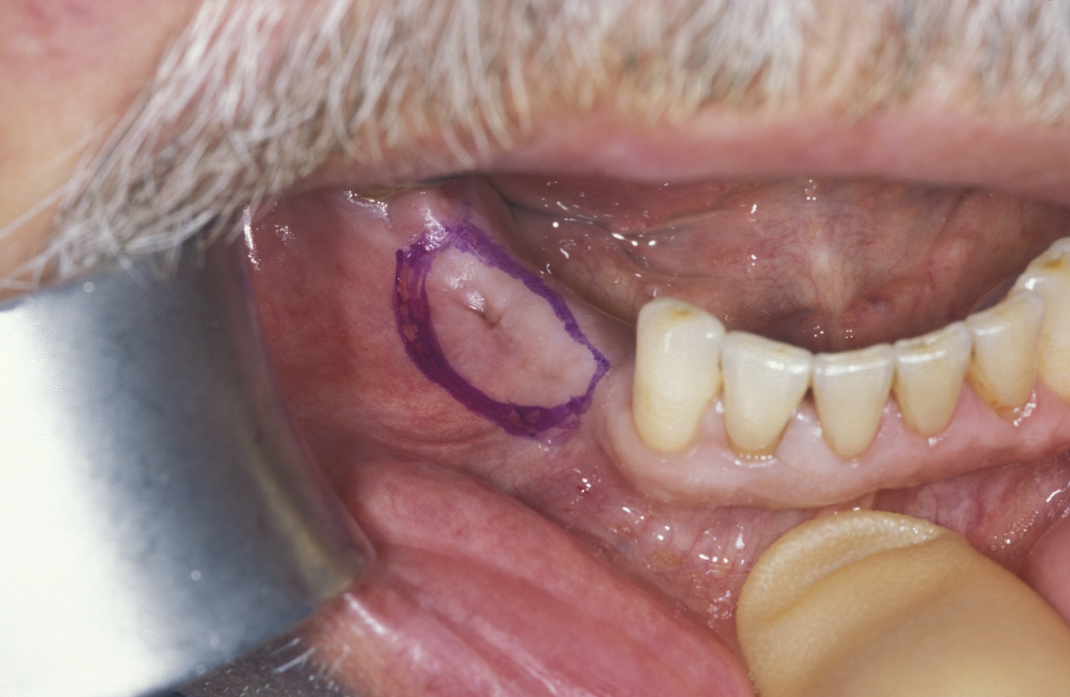

Large cysts in which enucleation may result in extensive local damage or patients who are unfit for more extensive surgery can be managed by marsupialization. This involves exposing the cyst lining and removing a small window from the lining. This is then sutured to the mucosa. The cavity can then be packed with an antiseptic dressing and regularly changed as the cavity heals from underneath. A step by step illustration of the procedure is shown in Figures 7 to 9.

Figure 7: Marsupialization of a cyst that is in contact with the overlying mucosa. The area of mucosa to be excised is marked (in purple).